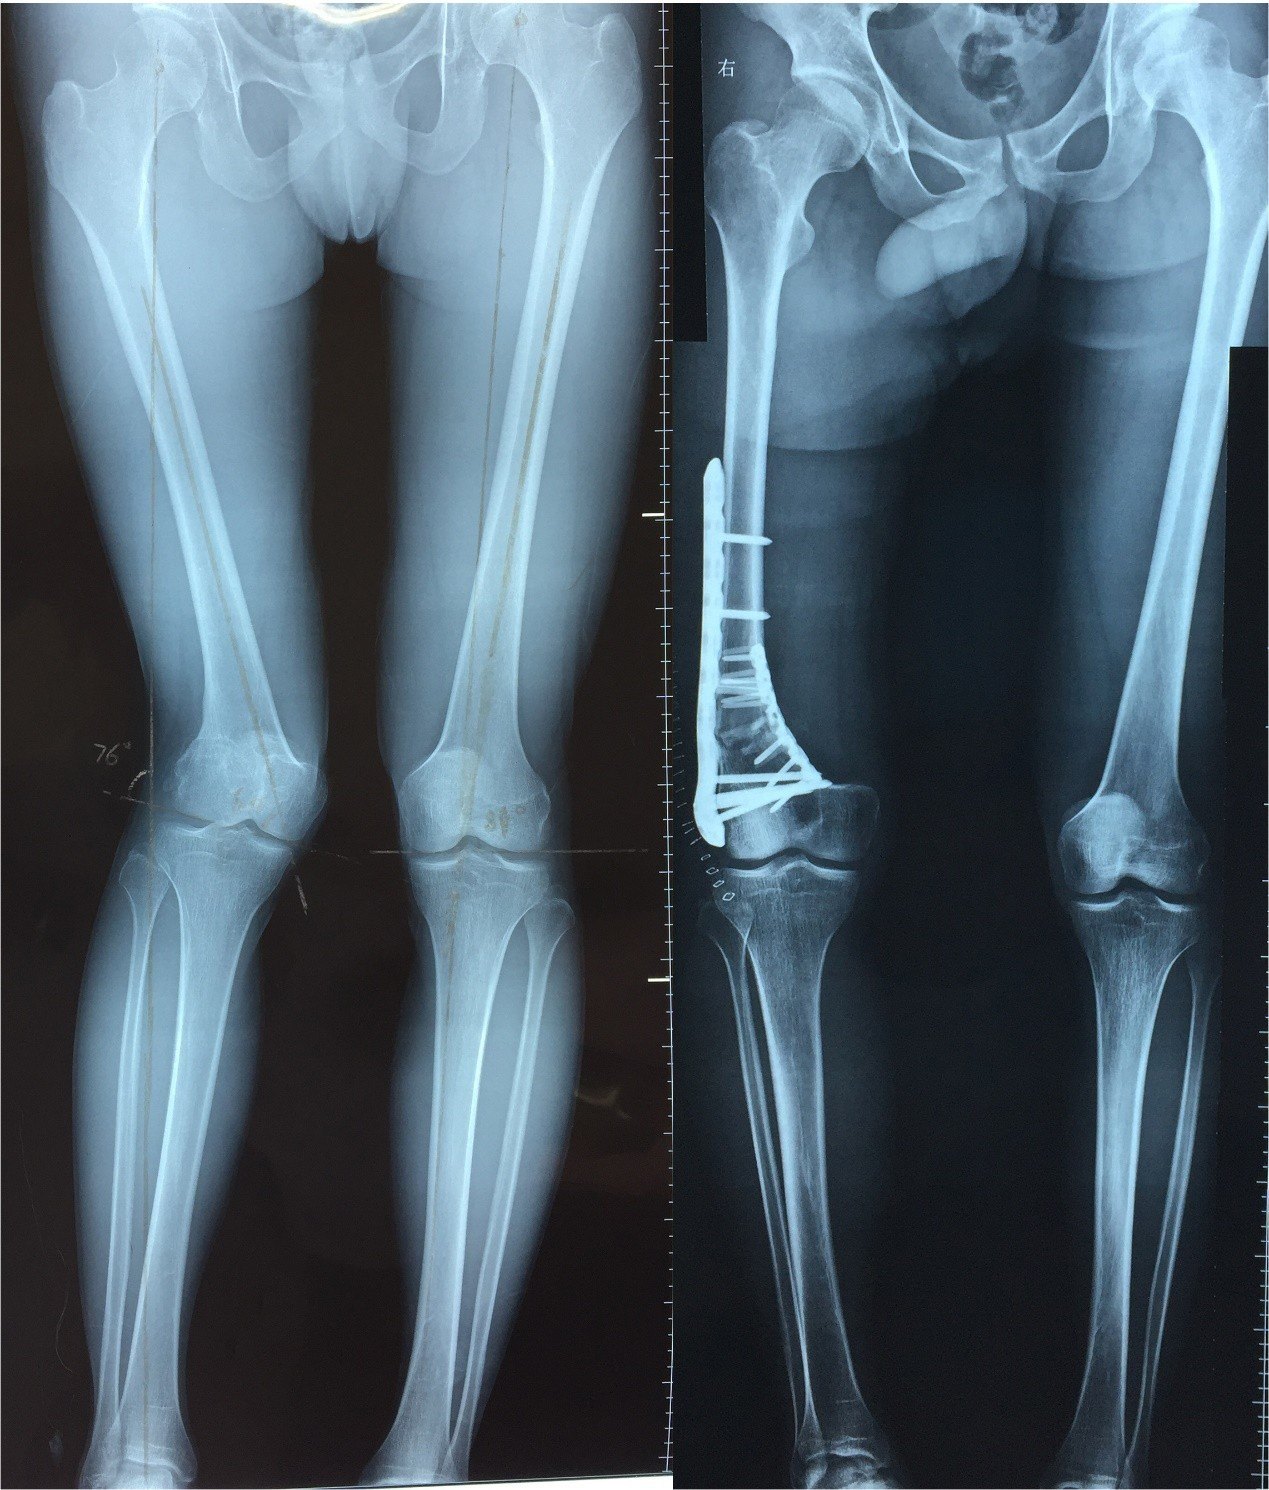

求助:儿童股骨干骨折畸形愈合

图片尺寸1200x1600